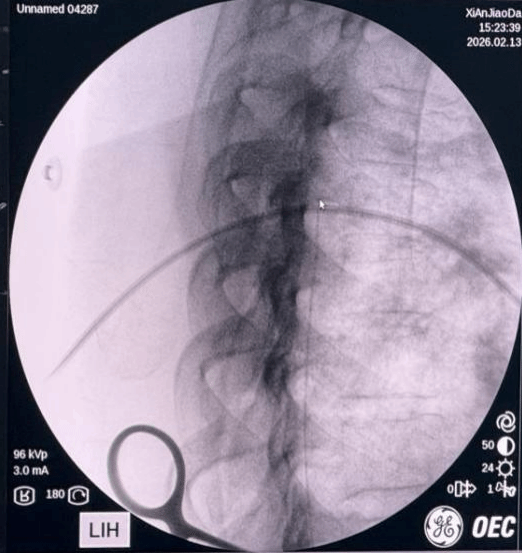

图1 鞘内镇痛泵导管置管操作

图3 透视确认导管端植入目标节段